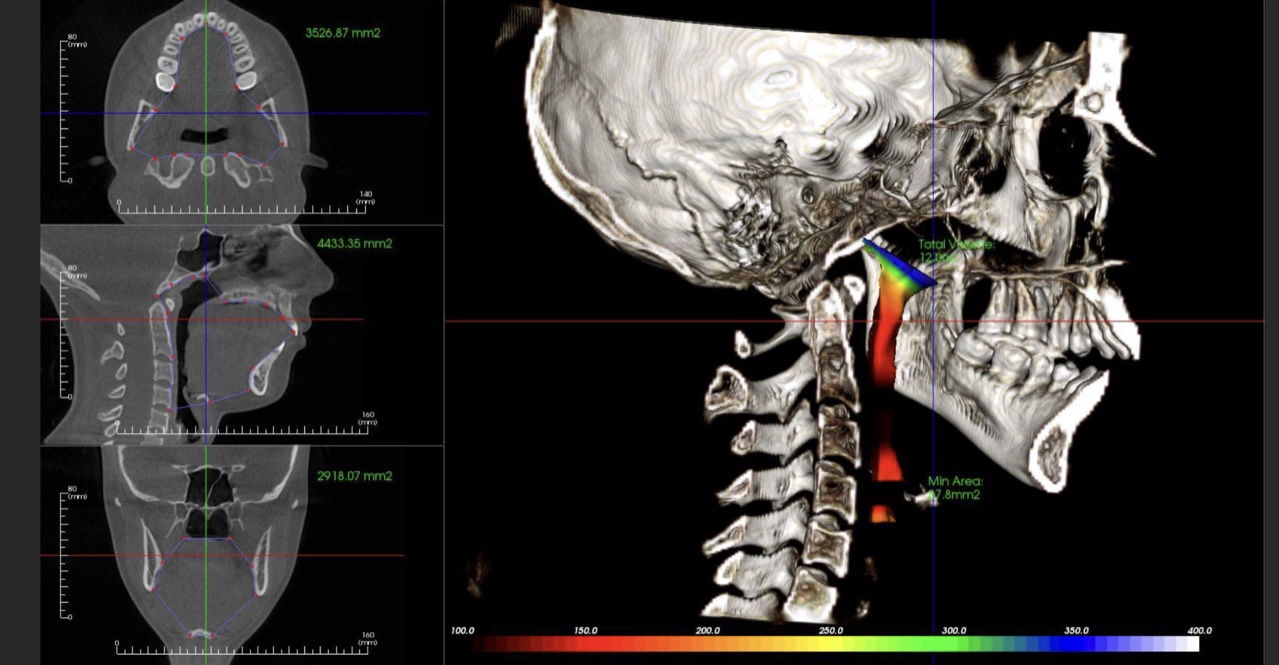

- The importance of imaging and its role in your specific diagnosis and risk assessment

- How to take, order and interpret both CT/MRI images